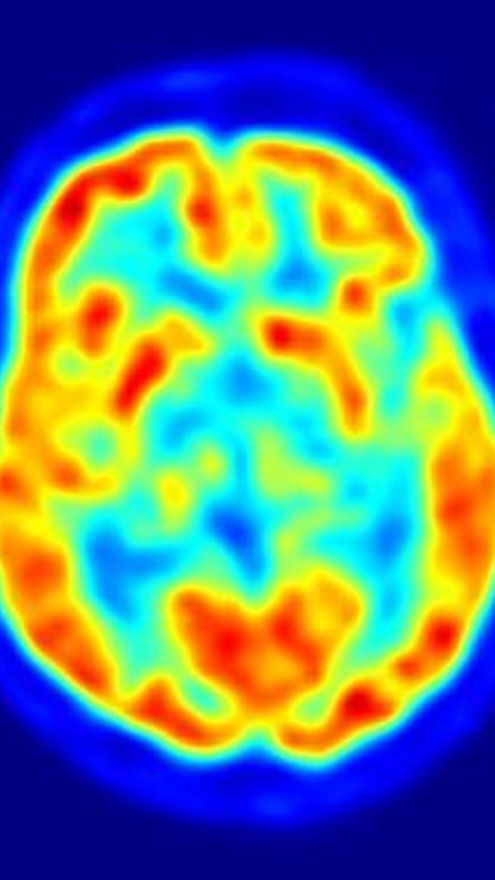

El altruismo depende de una región del cerebro

Las diferencias en el comportamiento altruista están relacionadas con la variación en el tamaño y la actividad de una región del cerebro involucrada en la empatía, según un estudio publicado en la revista 'Neuron'. Los resultados también proporcionan una explicación sobre por qué las tendencias altruistas se mantienen estables en el tiempo.

Las personas con facilidad para comprender a los demás son más altruistas; esta capacidad para comprender las perspectivas de otros ha sido previamente asociada con la actividad en una región del cerebro, conocida como unión temporoparietal (TPJ, por sus siglas en inglés). Basándose en estos hallazgos anteriores, Fehr y su equipo se dispusieron a analizar la relación entre el tamaño y la activación de TPJ, y las diferencias individuales en el altruismo.

En el nuevo estudio, los investigadores sometieron a los sujetos a un escáner de imagen cerebral, y les plantearon un juego en el que tenían que decidir cómo repartir dinero, entre ellos mismos y socios anónimos. Los sujetos que tomaron las decisiones más generosas mostraban un TPJ más grande, en el hemisferio derecho del cerebro, en comparación con los sujetos que tomaban las decisiones más egoístas.

“La estructura de TPJ predice con precisión el comportamiento altruista de un individuo”, concluye el coautor del estudio, Yosuke Morishima, de la Universidad de Zurich.